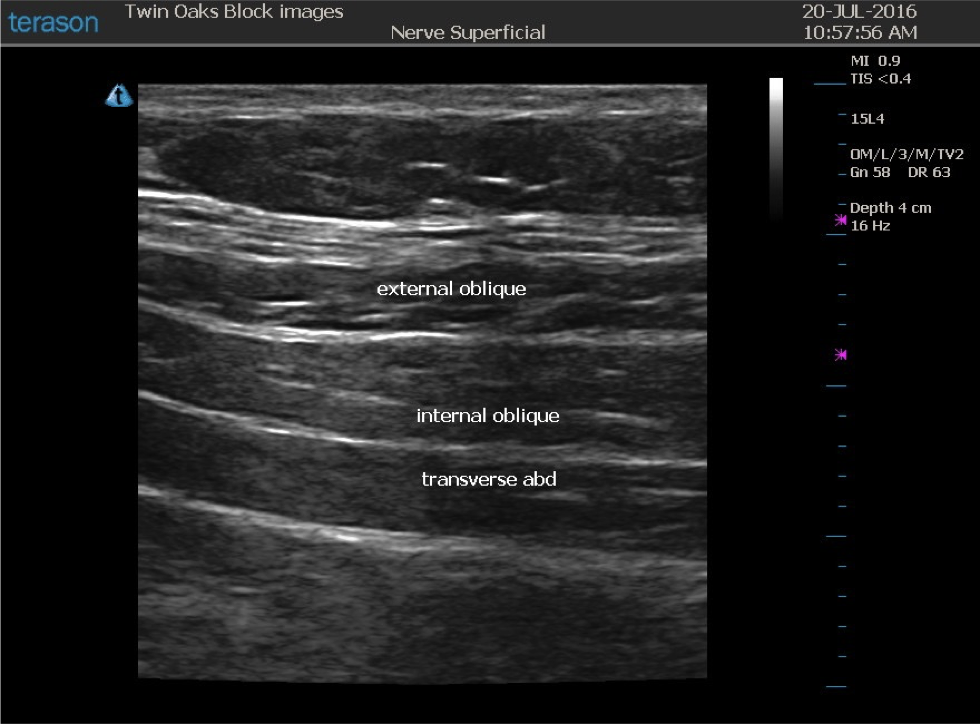

From www.twinoaksanesthesia.com

TAP Block — CRNA Conferences Twin Oaks Anesthesia Tap Block Procedure Tap blocks are a great adjunct to a multimodal. A tap block is a procedure that injects anesthesia into a space in your abdominal muscles to block pain from your incision. Subcostal tap block is performed by placing the probe just beneath the costal margin and parallel to it. Utilizing ultrasound, transversus abdominis plane (tap) blocks can provide reliable relief. Tap Block Procedure.